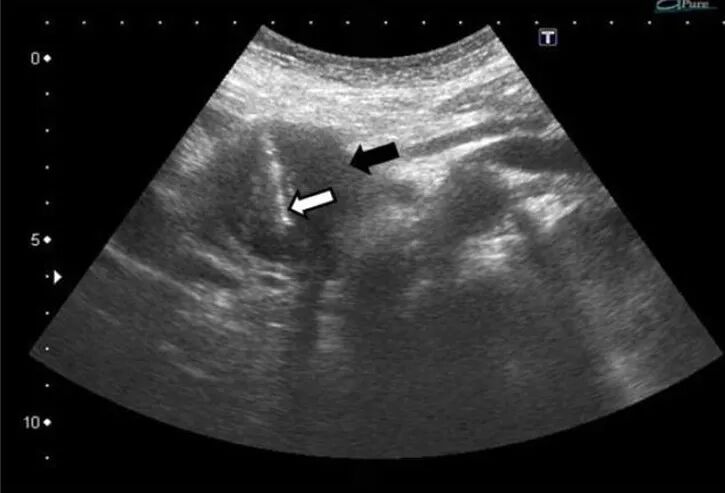

在超声的实时引导下应用穿刺针或活检枪经皮刺入肿块内,获取细胞或组织标本。 ①疾病诊断 明确肿瘤的良恶性、明确肿瘤的组织学来源和分型、鉴别原发肿瘤或转移性肿瘤。 ②指导治疗方案 对取得的标本进行免疫组化、基因检测,指导靶向、免疫或化疗药物选择。 ③肿瘤的局部治疗 通过该技术可将抗肿瘤药物(如溶瘤病毒)直接注射到实体瘤内;囊性的肿瘤也可通过该技术进行穿刺引流减轻压迫症状。 ①创伤小 伤口仅如针孔大小。 ②安全 操作时间短,并发症少,耐受性好。 ③报告准确迅速 现场评价取材满意度,第二天即可获得细胞病理报告。 ④花费低 减轻家庭负担。 ①肝脏占位 ②胰腺占位 ③腹盆腔占位 ④浅表肿块 ⑤肿大淋巴结等 穿刺活检针的针芯外层设计为保护套管,切取肿瘤组织后,套管将肿瘤组织封闭在针芯内,隔离了肿瘤组织和正常组织接触的机会,避免种植转移。